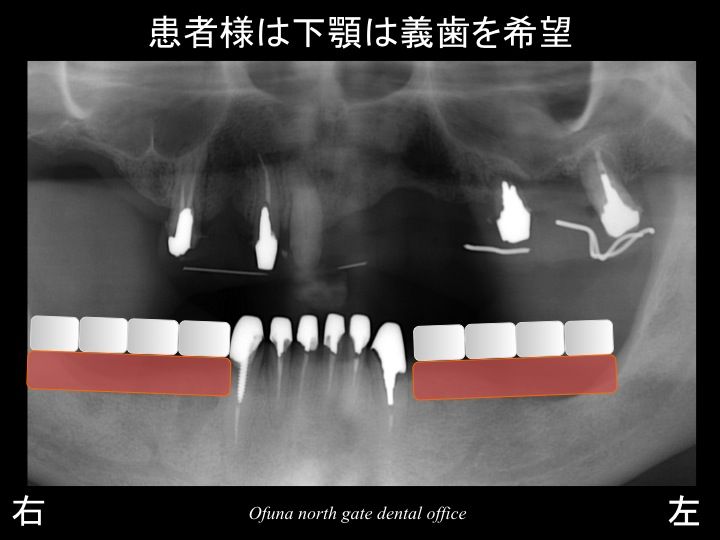

患者様は、上顎は義歯(入れ歯)ではない、固定式の治療をご希望されていました。

この場合、インプラント治療 と 天然歯でのブリッジ が考えられます。

以下のような治療法です。

上顎右側の3歯欠損には、3本のインプラントを埋入、

上顎右側の前歯は、ブリッジ、

上顎左側の前歯部には、3本のインプラントを埋入し4歯分を作製するブリッジ、

上顎の左側の奥歯は、天然歯のブリッジ

です。